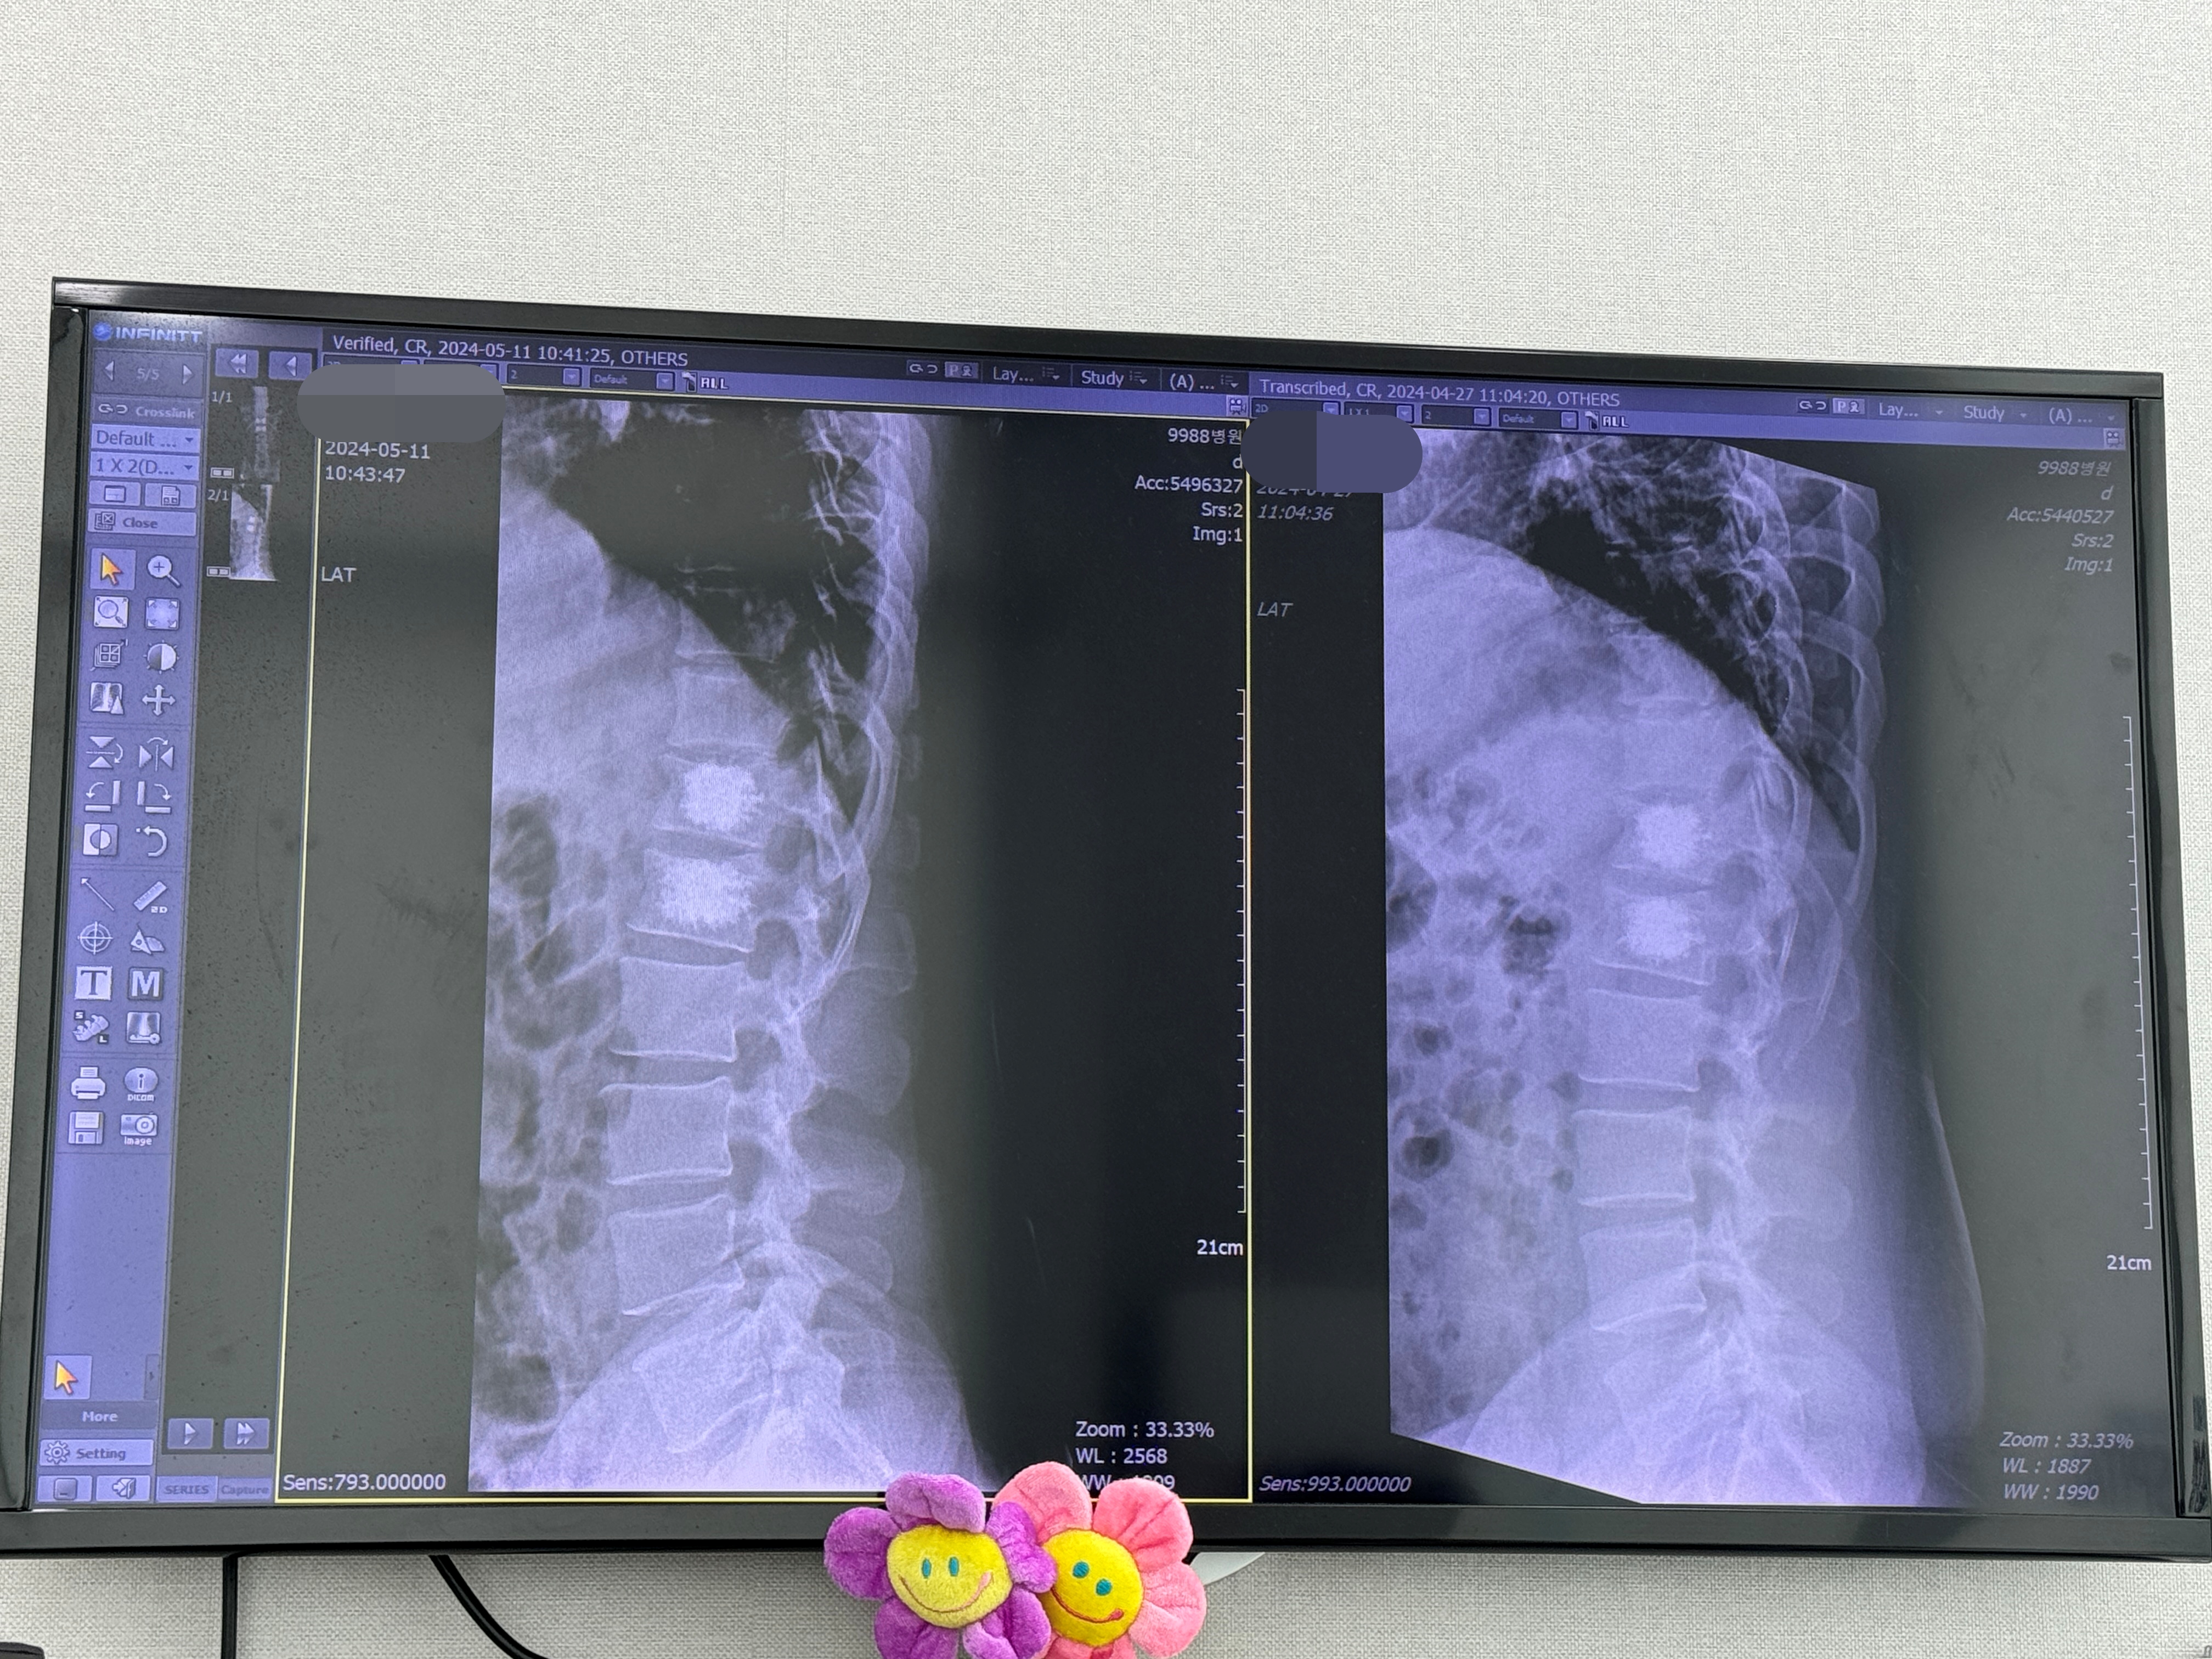

역시나 이전 내원처럼 뼈 상태를 확인하기 위해 X-RAY 먼저 촬영하고 옵니다.

그래서 토요일이 아닌 금요일 오후를 선호합니다. 사진 촬영과 동시에 바로 진료실로 들어가서 선생님을 뵙네요. 사진상으로도 2주 전이나 이전이나 다행히 뼈에 큰 변화는 없으니 이제 보호대를 벗자고 합니다. 감격스러운 순간입니다. 보호대를 벗고, 약은 그대로 먹고 2주 뒤에 보자고 하네요.